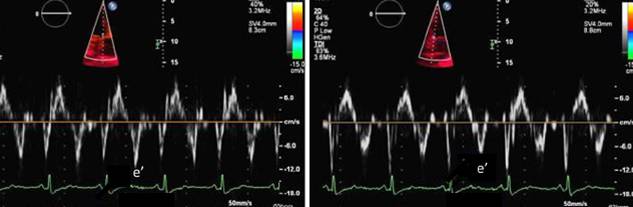

组织多普勒e’

缩窄性心包炎